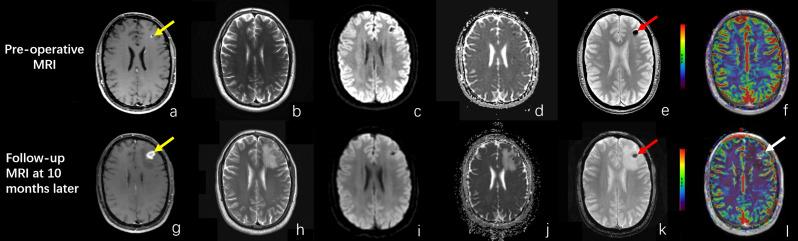

Pseudoprogression is an atypical imaging pattern of response to immunotherapy in patients with brain tumors. MR perfusion studies in this field are limited. The purpose of our study is to compare the perfusion features between pseudoprogression lesions in malignant gliomas and brain metastases treated with immunotherapy (iPsP) and the pseudoprogression after chemo-radiation therapy and radiation necrosis after radiation treatment (ChR-PsP & RN).

We retrospectively reviewed 25 iPsP lesions in 16 brain tumor patients and 48 ChR-PsP & RN lesions in 35 patients. The cerebral blood volume (CBV) of MR dynamic susceptibility contrast (DSC) perfusion weighted imaging (PWI) was analyzed, and the mean and maximal values of the ratio of CBV (rCBV and rCBV) of iPsPs and ChR-PsP & RNs were calculated and compared between these two groups using the Mann-Whitney U test. A receiver operating characteristic curve analysis was conducted, and the optimal cutoff of perfusion parameters were determined using the area under the curve, sensitivity, and specificity.

The medians of rCBV and rCBV in iPsP group were significantly higher (0.94 and 1.39 respectively) than ChR-PsP & RN group (0.67, p < 0.01 and 1.1, p = 0.01 respectively). The rCBV value of 0.69 can differentiate the iPsP from ChR-PsP & RN with the area under the curve of 0.71, sensitivity of 0.72, and specificity of 0.56.

These findings may suggest immunotherapy-induced higher perfusion in the iPsP lesions compared to ChR-PsP & RN lesions in primary and metastatic brain tumors.